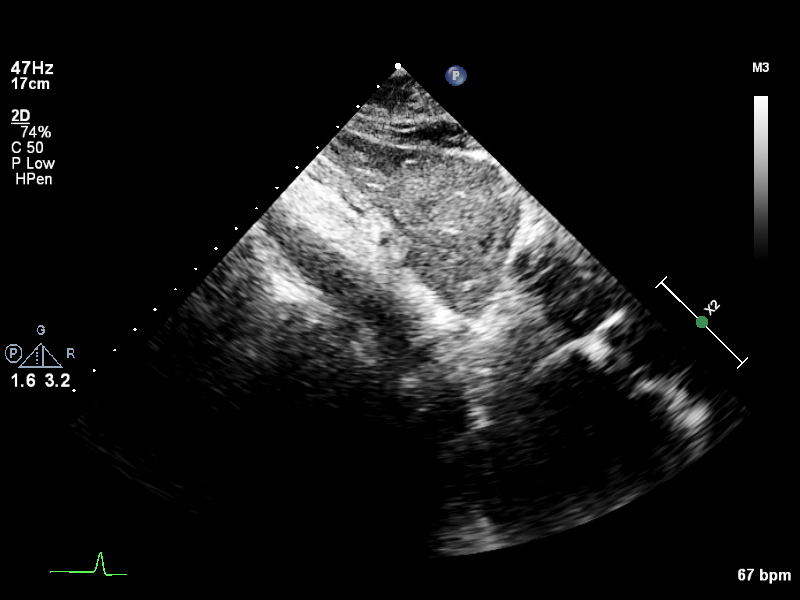

Subcostal & Suprasternal (3 views)

subcostal-heart subcostal-heart Subcostal window, focused on the heart